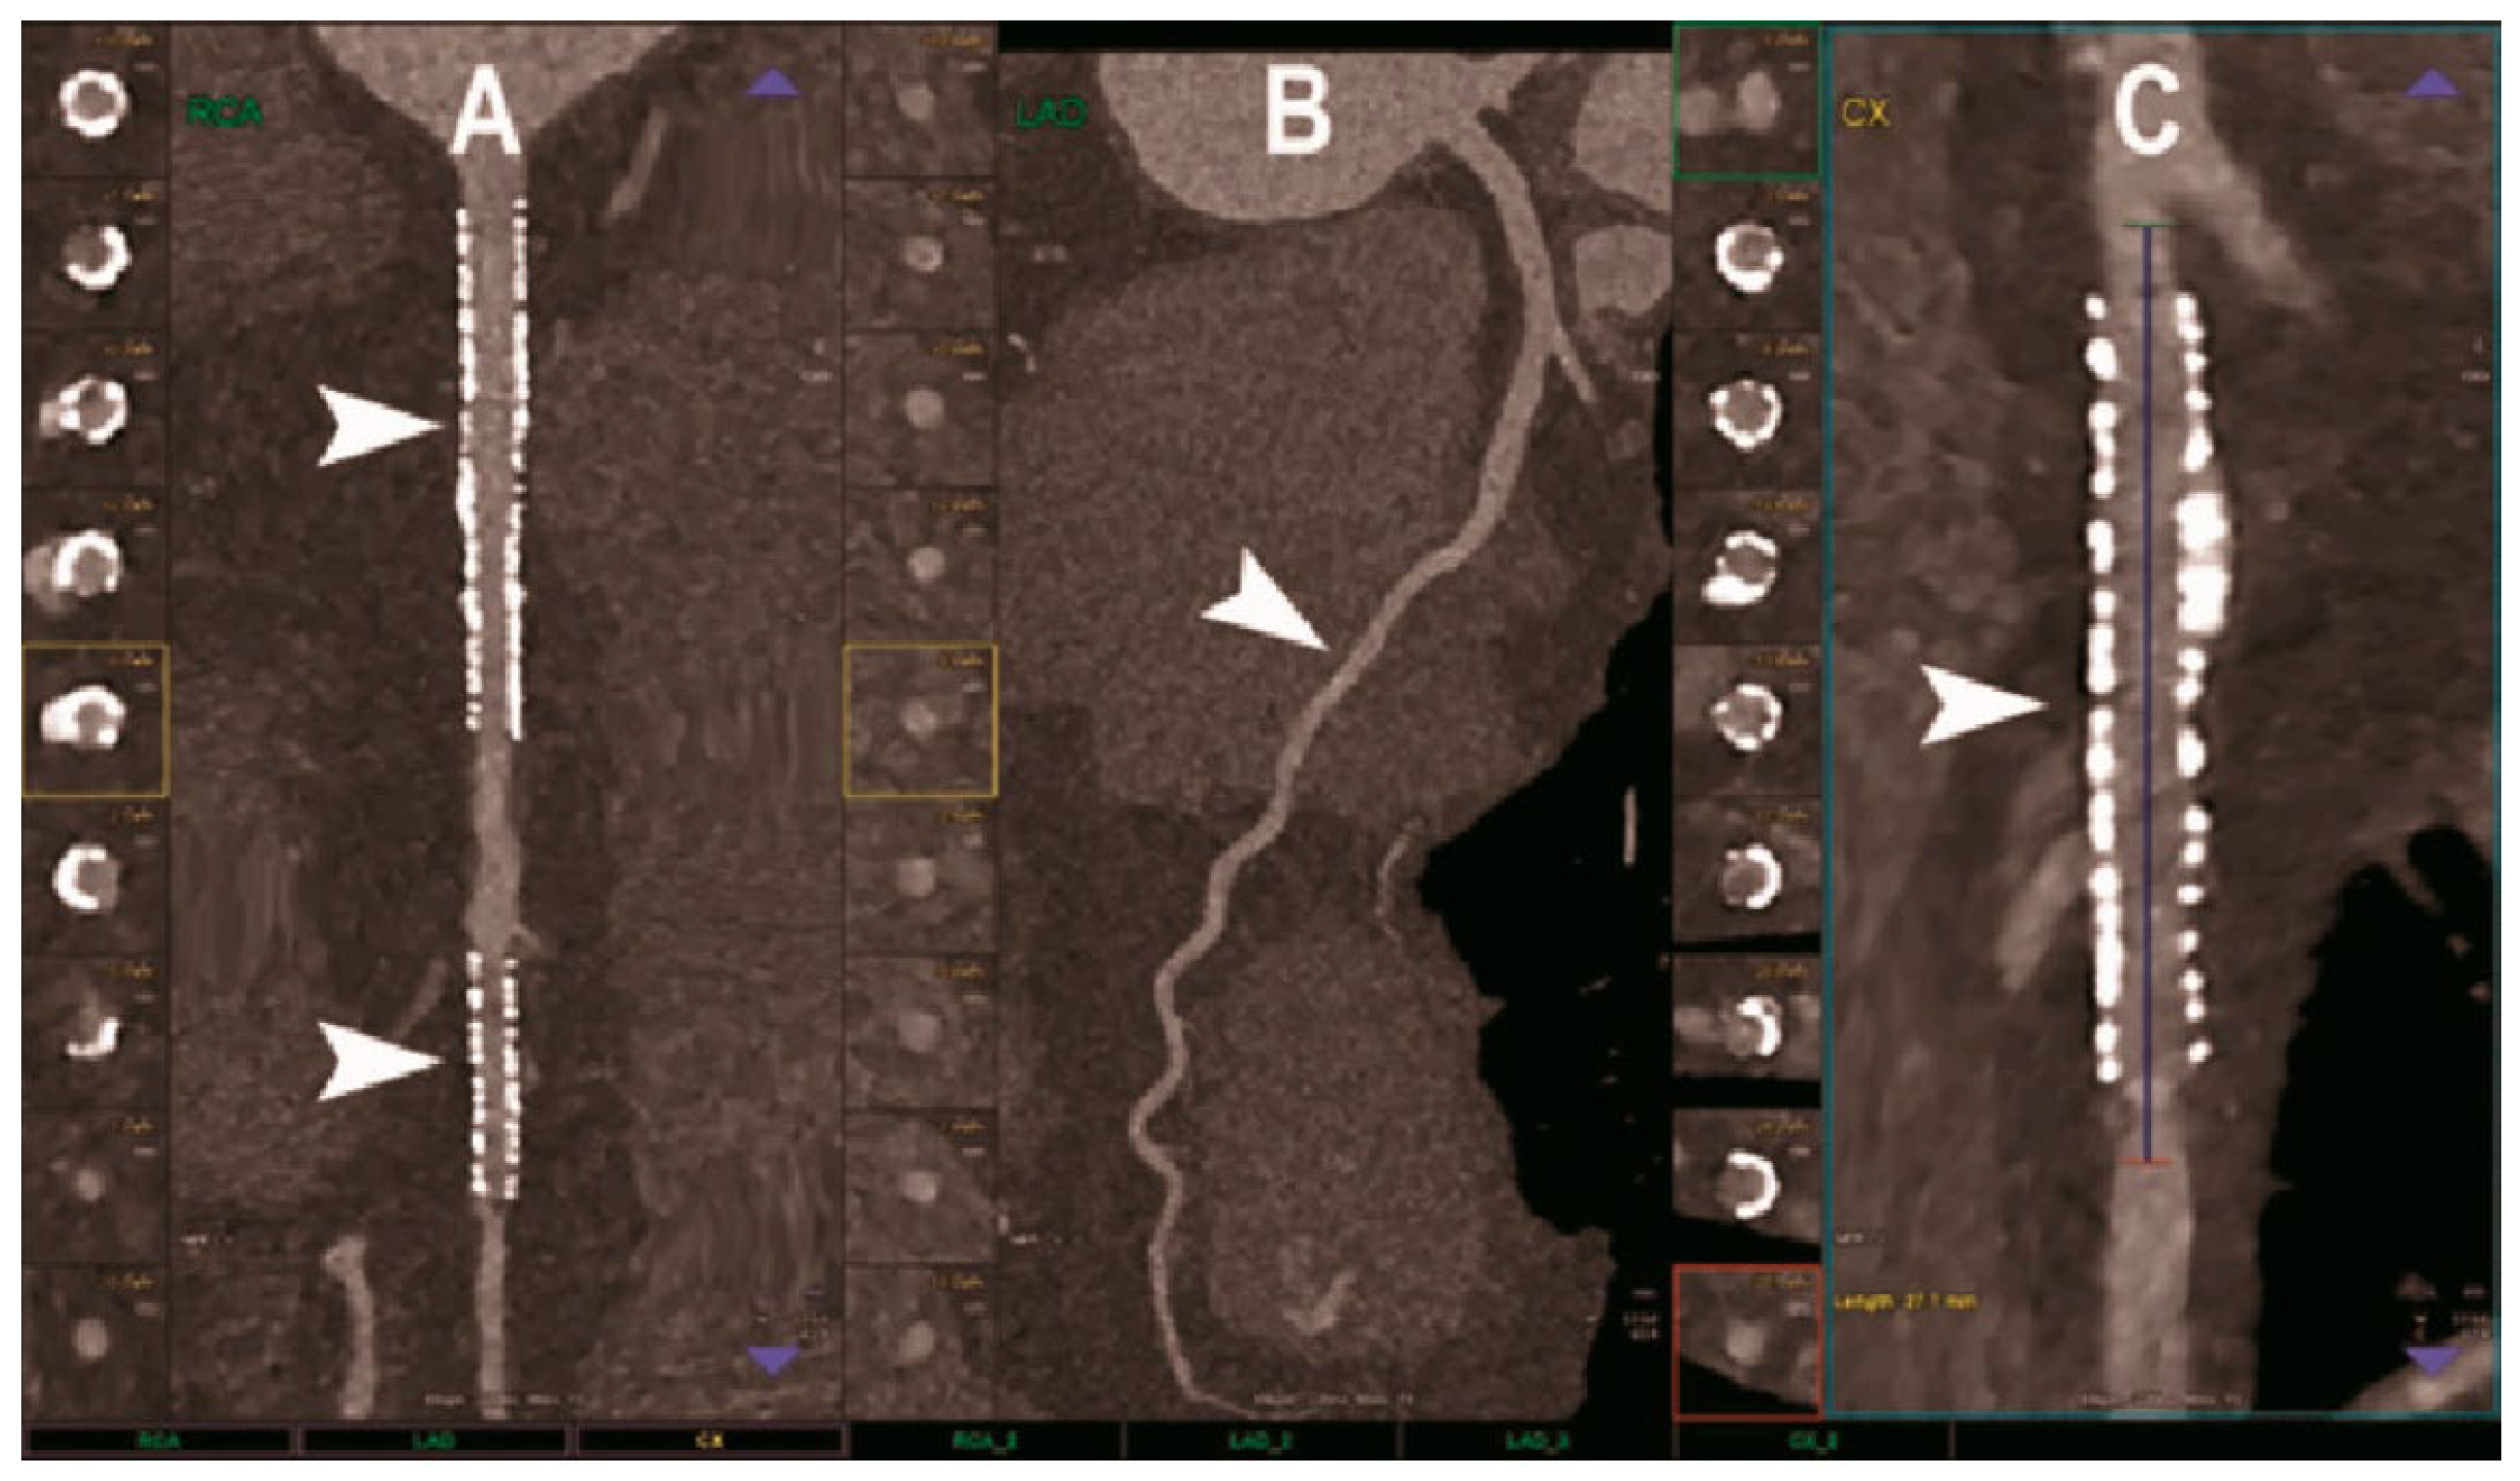

The effective execution and operation of intracoronary imaging modalities during these procedures improve both procedural and long-term clinical outcomes, particularly in intravascular ultrasound (IVUS) (Figure 6 and Figure 7) and optical coherence tomography (OCT) (Figure 8 and Figure 9), where coronary lesion morphology and mapping facilitate better PCI procedural planning [46]. Both IVUS and OCT can detect, localize, and quantify coronary calcification. Notably, OCT can visualize the calcified plaque without producing visual imaging artifacts, thereby minimizing observational scatter, and can evaluate calcium thickness more accurately than IVUS.

A 3D calcium evaluation displaying a color-coded visual depiction of calcified plaques utilizing coronary CT imagery is a remarkable feat that analyzes the calcium plaque’s location relative to the circumference of the coronary vessels while computing the location of the vessel wall in relation to the superior (epicardial) or inferior (myocardial) borders [44]. The 3D calcium evaluation through CT imagery is a tool that gauges the coronary tree’s curvature, tortuosity, and radius while assisting in predicting the path of the guide wire to prevent or minimize contact with calcium plaque deposits within the vessel.